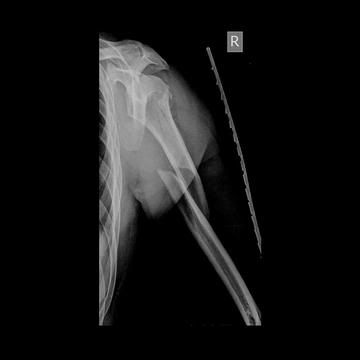

Broke my arm

9 days ago. Fall at work offshore in Nigeria. 12 weeks off work now